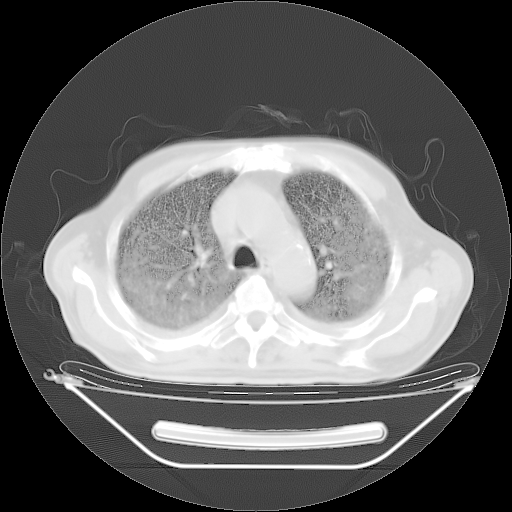

今天复查肺部CT,发现双肺广泛磨玻璃样改变。所以我把3月19日和5月9日相隔50天的肺部CT上传。请大家会诊。

5月9日肺部CT(在4月27日齐鲁医院肺部CT描述部分肺组织磨玻璃样改变,12天后肺组织广泛磨玻璃样改变)

大致读了系列胸部CT:纵隔窗无明显异常,肺窗:从4、27至今:主要是双肺中下野外带可见毛玻璃样改变,目前处于急性肺泡炎阶段,至于原因考虑1、结替组织或胶原血管性疾病所致?2、恶性疾病如恶组在肺部所致的表现或细支气管肺泡癌?3、药物或其它原因如肺蛋白沉着症所致肺泡炎目前不太可能?总之,明天就去请我院的呼吸科、感染科、血液科和临免专家会诊哈。